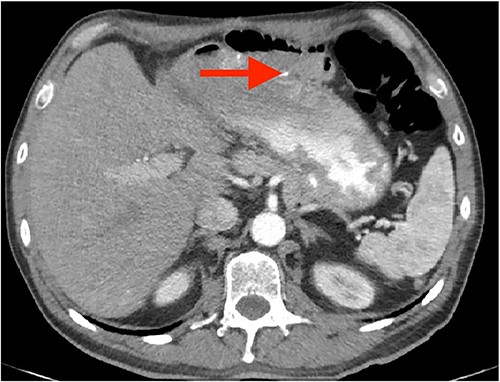

A 57-year-old white male reached for medical advice after 15 months of progressive dysphagia and weight loss. The patient had a history of ‘kissing’ duodenal ulcers (DU) which caused perforation with concomitant posterior DU bleeding 10 years ago; at the time he underwent exploratory laparotomy and gastroduodenal artery (GDA) ligation as well as ‘Graham patch’ procedure for the perforated DU. A few months later the patient developed pyloric stenosis and gastric outlet obstruction, for which he was treated with re-exploration and gastrojejunal anastomosis-bypass (Fig. 1). Clinical symptoms of dysphagia, regurgitation and reflux led to esophagogastroduodenoscopy 2 months prior to admission, which revealed esophageal lumen stenosis, Barrett’s esophagus and a sizeable mixed type hiatus hernia. Endoscopically acquired biopsy confirmed high-grade dysplasia on the background of Barrett’s esophagus, progressing to invasive esophageal adenocarcinoma. His past medical history was significant for a 4.4 cm infrarenal abdominal aorta aneurysm and hypertension. The patient was admitted to the hospital for nutritional support and further preoperative evaluation. Contrast-enhanced computed tomography (CT) angiography performed to evaluate vasculature of the stomach revealed absence of the RGEA as expected since GDA was ligated in his previous operation (Fig. 2).After complete staging and multidisciplinary meeting discussion the decision was to proceed with primary surgery. Histopathology exam revealed a gastroesophageal adenocarcinoma staged as pT3N1 [3].

Coronal CT images of stomach’s vascular supply (arrows showing RGEA absence).